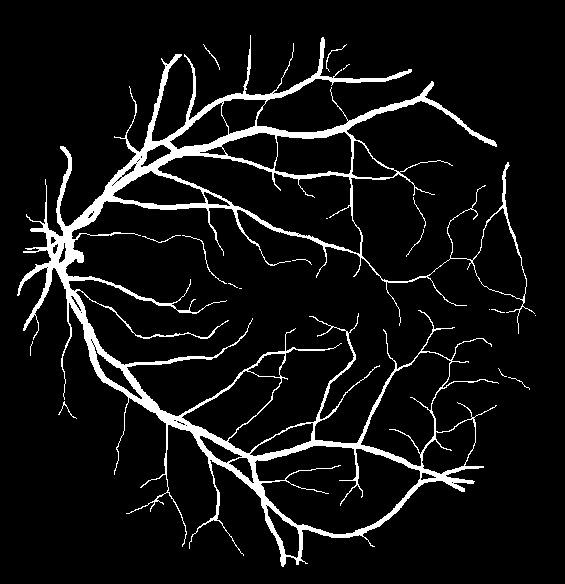

This is the image that i need to segment. There is already segmented images just for comparison purposes ,With explanation